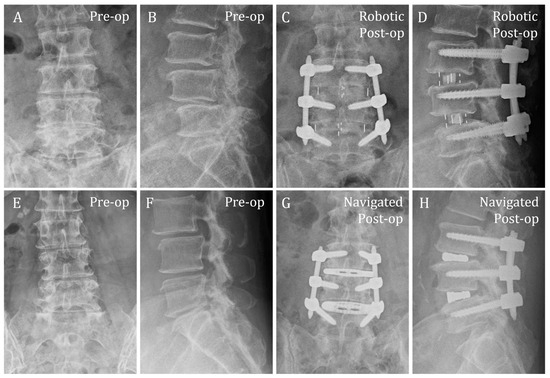

| Pair No. | Robotic/Navigated | No. of Levels | Technique | Diagnosis | Decompression (Direct vs. Indirect) | Single or Dual Position | Duration (min) | p-Value |

|---|---|---|---|---|---|---|---|---|

| 1 | Robotic | 1 (L5-S1) | MIS TLIF | Degenerative | Direct | Single | 293 | 0.21 |

| Navigated | 235 | |||||||

| 2 | Robotic | 1 (L4-L5) | MIS TLIF | Degenerative | Direct | Single | 230 | |

| Navigated | 195 | |||||||

| 3 | Robotic | 1 (L5-S1) | MIS TLIF | Degenerative | Direct | Single | 242 | |

| Navigated | 180 | |||||||

| 4 | Robotic | 1 (L4-L5) | MIS TLIF | Degenerative | Direct | Single | 247 | |

| Navigated | 220 | |||||||

| 5 | Robotic | 1 (L5-S1) | MIS TLIF | Degenerative | Direct | Single | 190 | |

| Navigated | 197 | |||||||

| 6 | Robotic | 1 (L4-L5) | OLIF | Degenerative | Indirect | Single | 210 | |

| Navigated | 225 | |||||||

| 7 | Robotic | 1 (L4-L5) | OLIF | Degenerative | Direct | Dual | 307 | |

| Navigated | 305 | |||||||

| 8 | Robotic | 2 (L4-S1) | MIS TLIF | Degenerative | Direct | Single | 310 | |

| Navigated | 298 | |||||||

| 9 | Robotic | 2 (L4-S1) | MIS TLIF | Degenerative | Direct | Single | 323 | |

| Navigated | 2 (L3-L5) | 372 | ||||||

| 10 | Robotic | 2 (L3-L5) | OLIF | Degenerative | Direct | Dual | 385 | |

| Navigated | 367 |